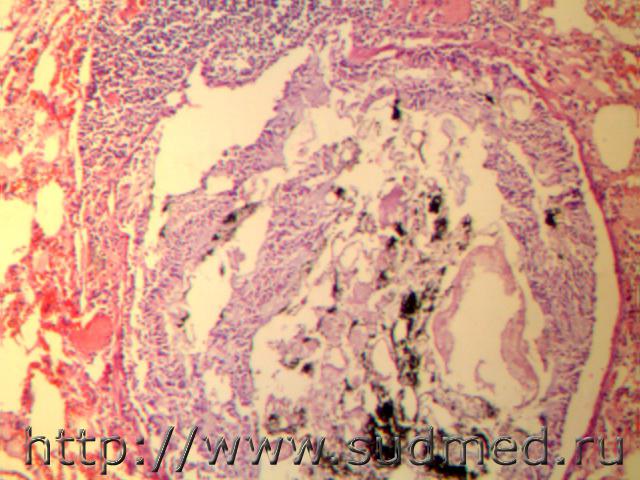

Дети 3 и 5 лет.После пожара, отравление угарным газом. Гранулы копоти черного цвета в толще слизи и в цитоплазме эпителии слизистой бронхов. Отек, эмфизема легких.